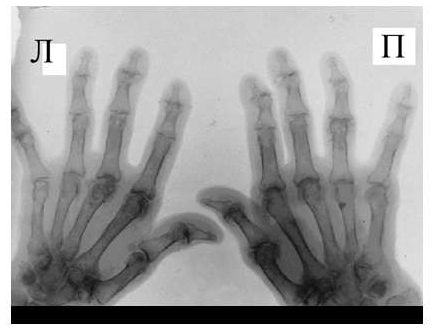

Рис. 5 Множественный остеолиз и деструкции эпифизов костей с разнонаправленными деформациями суставов при псориатическом артрите.

При развернутой картине болезни деструкция концевых фаланг (акроостеолиз) и чашеобразная деформация проксимальной части фаланг пальцев кистей вместе с концевым сужением дистальных эпифизов симптом «карандаш в колпачке» (рис. 5), множественный остеолиз и деструкции эпифизов костей с разнонаправленными деформациями суставов (мутилирующий артрит).